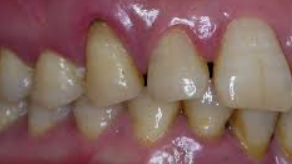

잇몸에 좋은 치약 추천

잇몸 건강은 전반적인 구강 건강의 핵심입니다. 잇몸 문제는 불편함과 통증을 초래할 뿐만 아니라, 심각한 경우 치아 손실로 이어질 수 있기 때문에 적절한 치약 선택이 중요합니다. 여기서는 잇몸에 좋은 치약을 선택하는 데 도움이 되는 몇 가지 팁을 제공합니다.

이러한 요소들을 고려하여 치약을 선택하면, 잇몸 건강을 유지하는 데 도움이 될 것입니다. 또한, 정기적인 치과 방문과 함께 올바른 양치질 습관을 유지하는 것이 중요합니다. 양치질은 3분에서 5분 동안 부드럽게 하고, 너무 세게 닦지 않으며, 집중적으로 한 곳만 닦지 않는 것이 좋습니다.

잇몸 건강을 위한 치약 선택은 개인의 구강 상태와 선호도에 따라 달라질 수 있으므로, 자신에게 맞는 치약을 찾기 위해 여러 제품을 시도해보고, 필요한 경우 치과 전문가와 상담하는 것이 좋습니다. 건강한 잇몸은 건강한 삶의 기초이므로, 적절한 치약 선택으로 구강 건강을 지키세요.